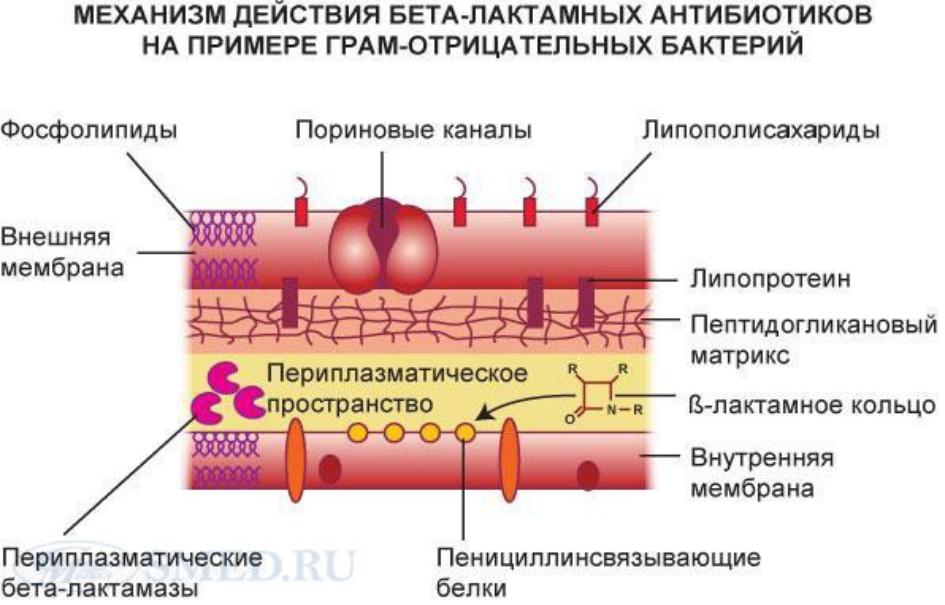

Механизмы действия антимикотиков: схемы и изображения